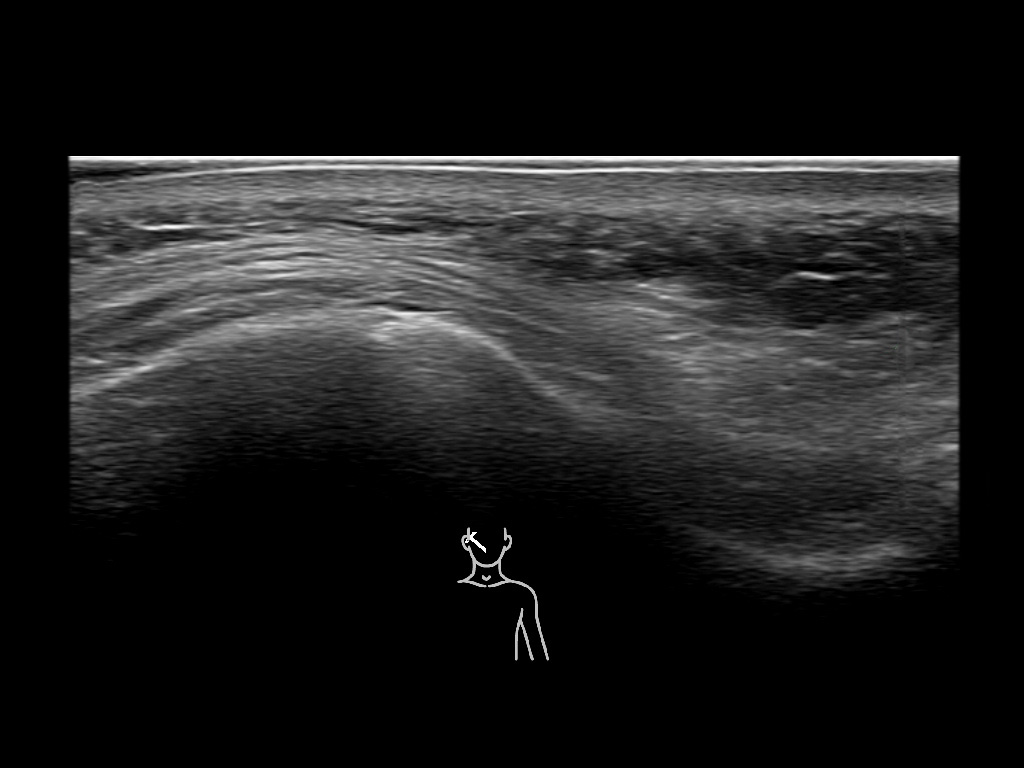

Study the first image to recognize the different layers. If you are sure about the layers, swipe to the second image to view the answer (if applicable).